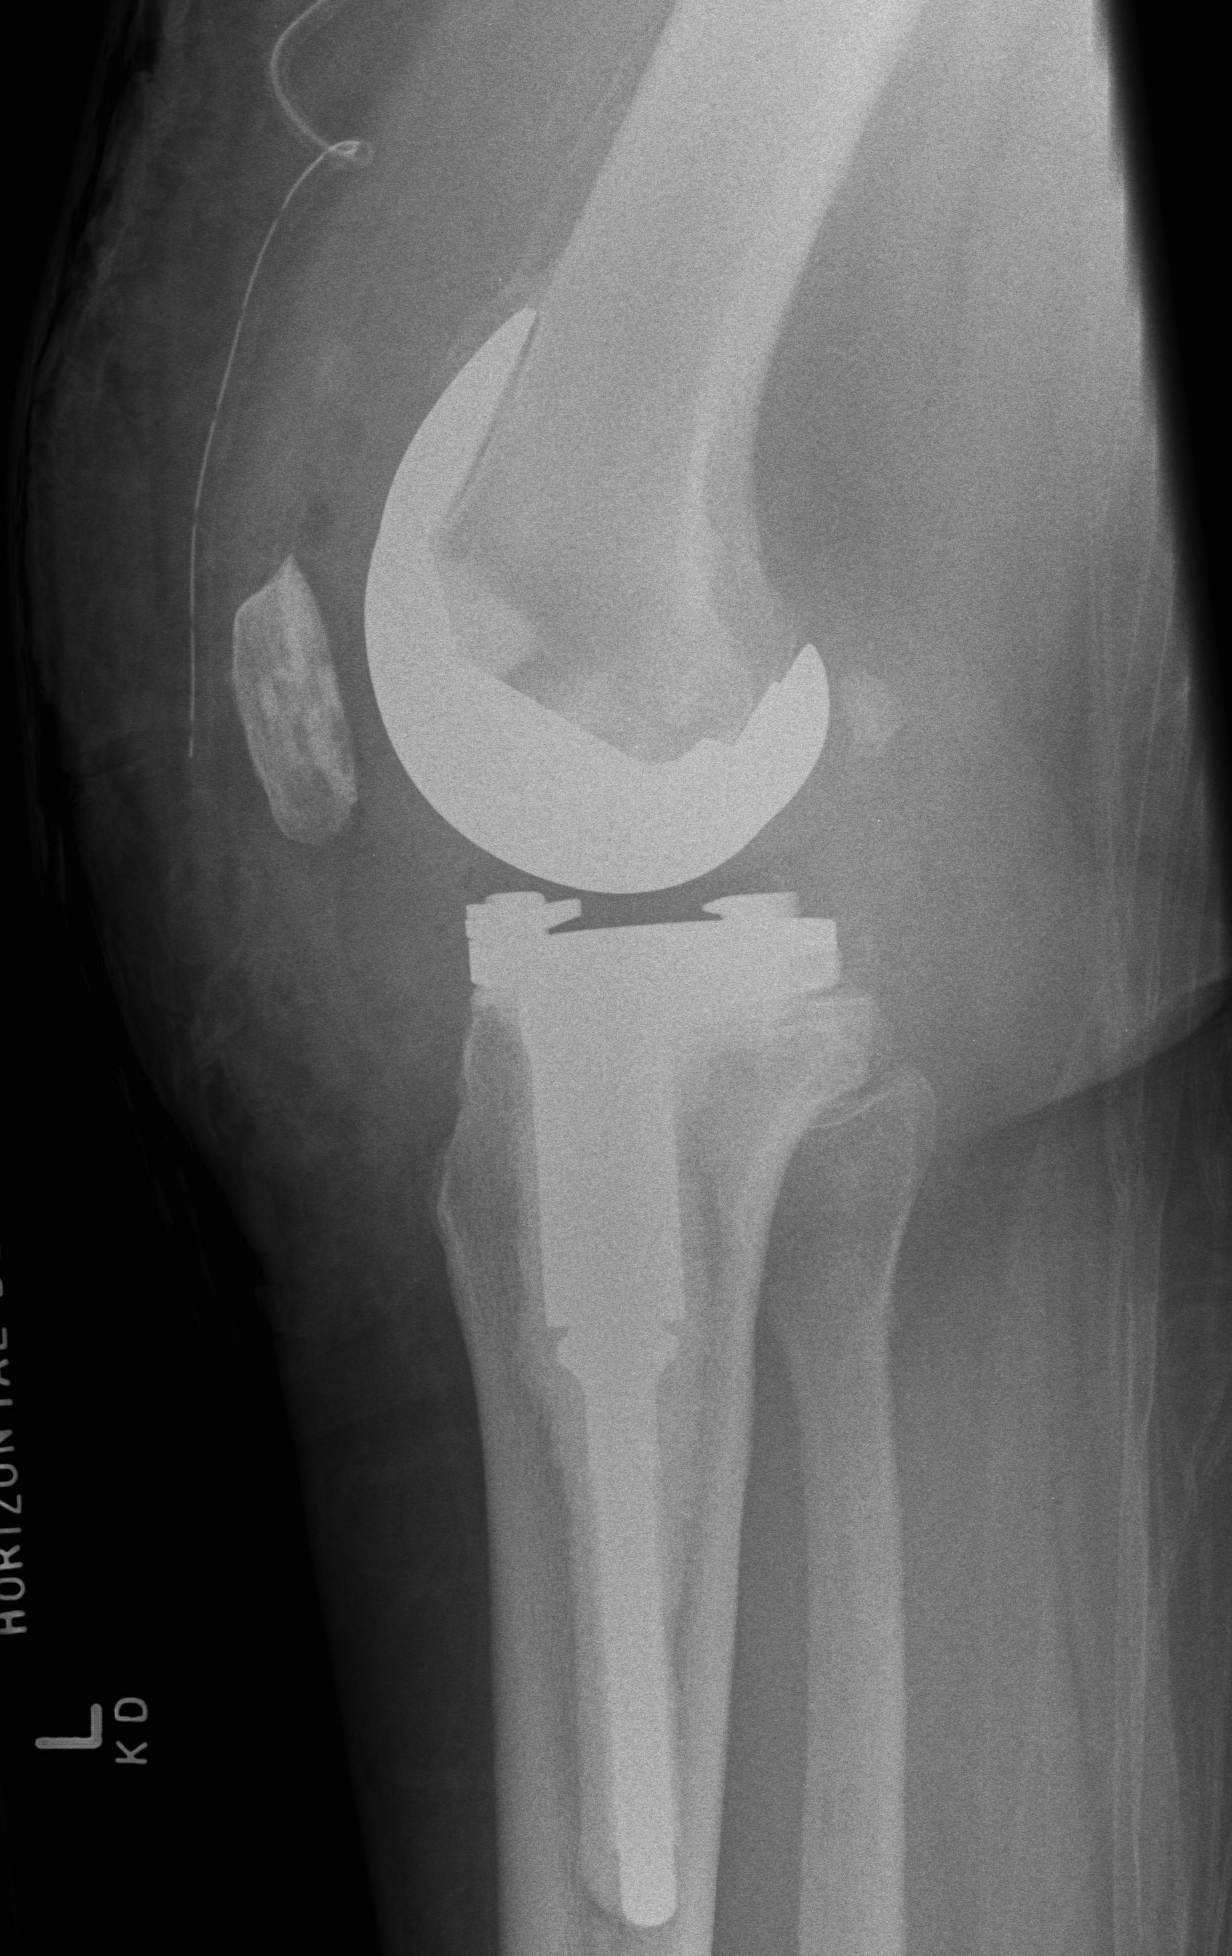

A. Bulk structural allograft

- femoral head

Engh et al JBJS Am 2007

- bulk structure allograft in the tibia in 46 patients followed for 8 years

- 2 deep infections

- average knee society scores 84

- no graft collapse or loosening

B. Tantalum cones metaphyseal filling / Trabecular metal

Howard et al JBJS Am 2011

- femoral tantalum components in 24 knees followed for averag 3 years

- knee society score average 81

- all well fixed with no complications